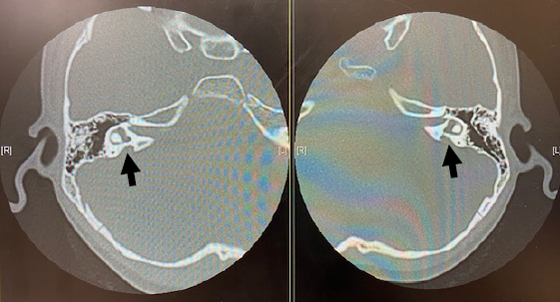

画像検査

CTやMRIなどの画像検査では先天性の中耳奇形や内耳奇形、蝸牛神経(音を脳まで伝えるための神経)の低形成などの診断ができます。